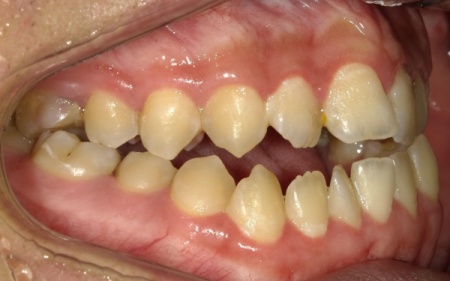

10代男性 顎変形症が原因で下顎がずれて非対称になっていた噛み合わせをサージェリーファースト法を併用した矯正治療で改善した症例

「顔と顎がゆがんでいて、見た目が悪くしゃべりにくいのが気になる。また、前歯が噛み合っていないため、食べ物を噛み切ることができない」とご相談いただきました。

拝見したところ、骨格の問題により下前歯が上前歯より前に出ている前歯部反対咬合と、前歯が開いて噛み合わないオープンバイトが認められました。

さらに、下顎の骨が右方向にずれて上下の歯が噛み合う面が斜めになっていることで、顔面の非対称も見られます。

これらは顎変形症と呼ばれる状態で、現在は食べ物をしっかりと噛む機能が大きく制限されているうえ、発音や見た目に悪影響が出ていました。